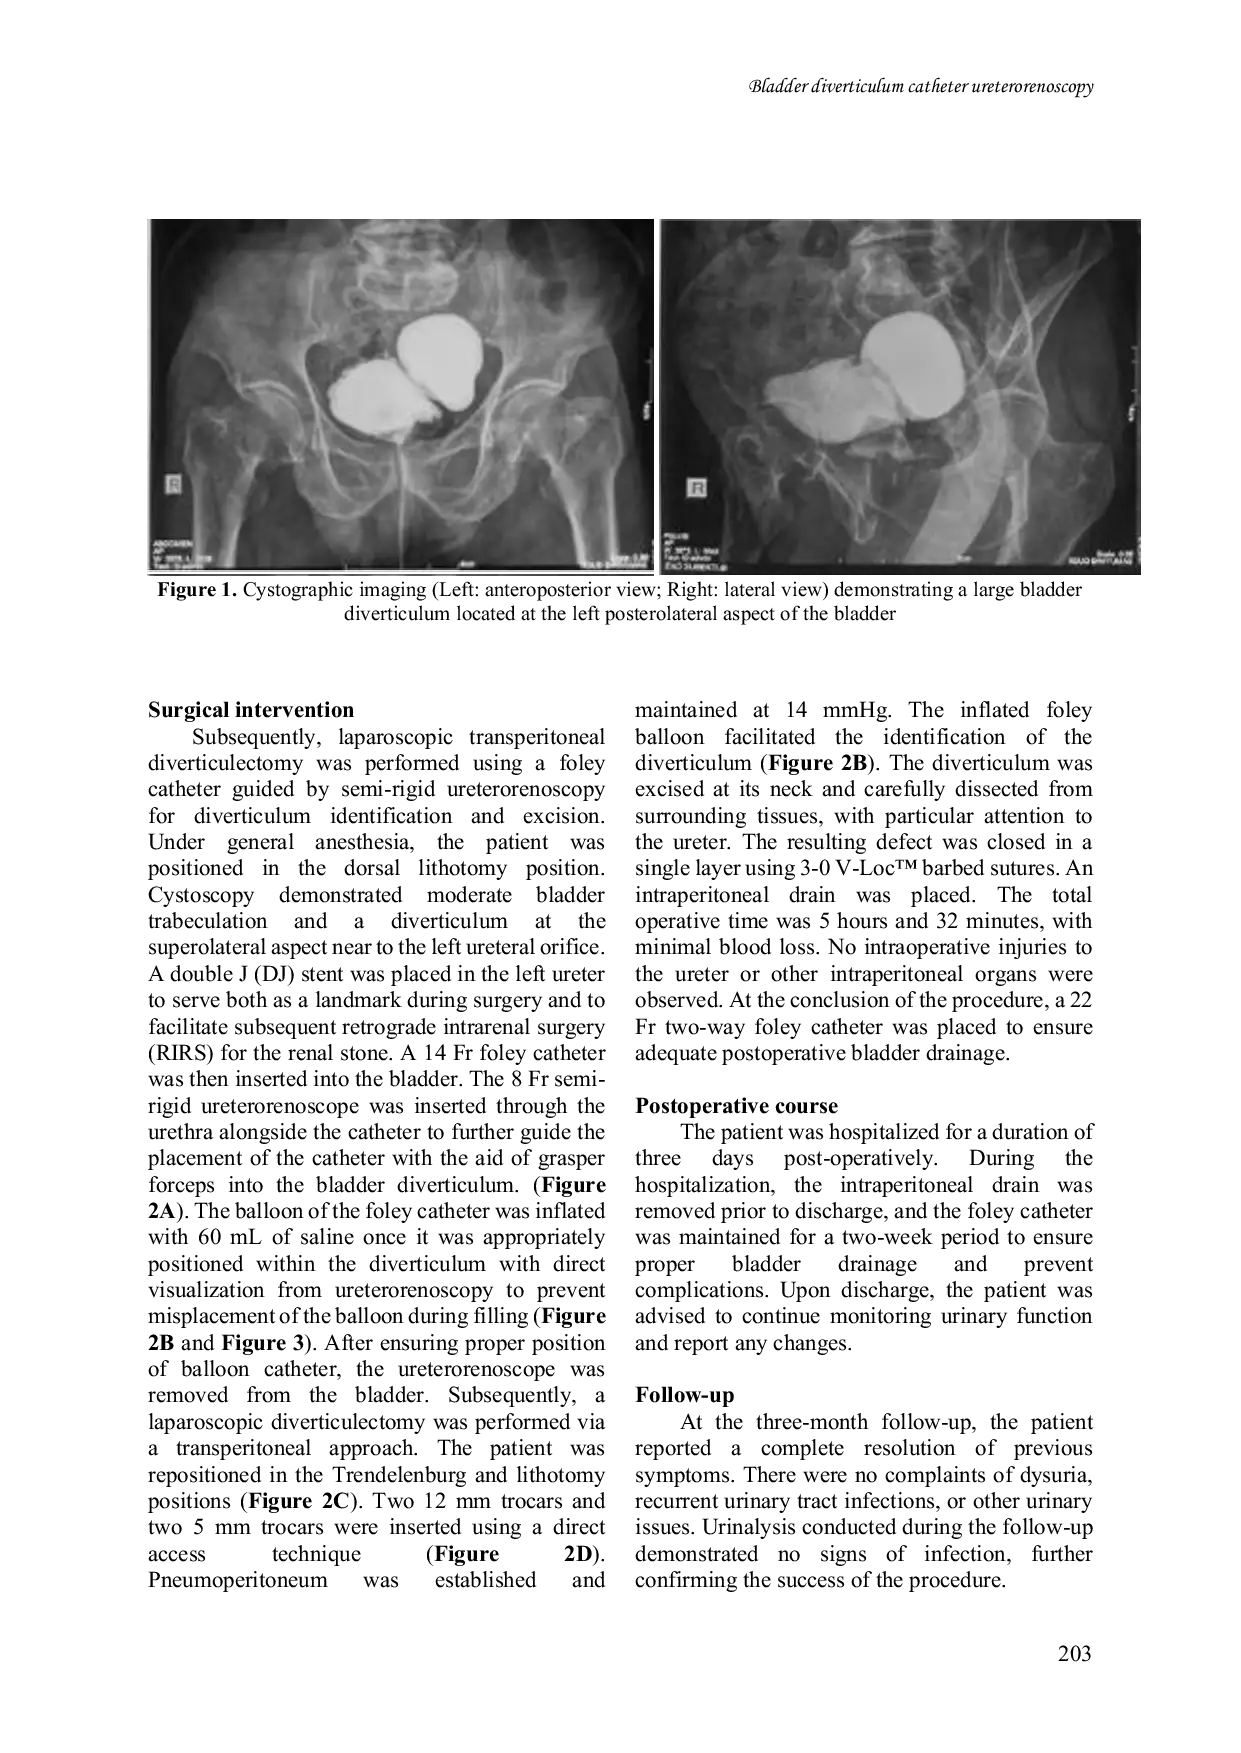

Universa MedicinaUniversa MedicinaLatar belakang: Divertikulum kandung kemih dapat menjadi akibat dari kelainan bawaan atau didapatkan sebagai akibat trauma, infeksi, atau obstruksi saluran kemih. Meskipun teknik laparoskopi telah mengalami kemajuan, identifikasi divertikulum secara intraoperatif tetap menjadi tantangan yang signifikan. Tujuan laporan kasus ini adalah untuk menawarkan teknik alternatif menggunakan kateter Foley yang dipandu oleh ureterorenoskopi semi-rigid untuk memfasilitasi identifikasi divertikulum kandung kemih selama divertikulectomi laparoskopik.